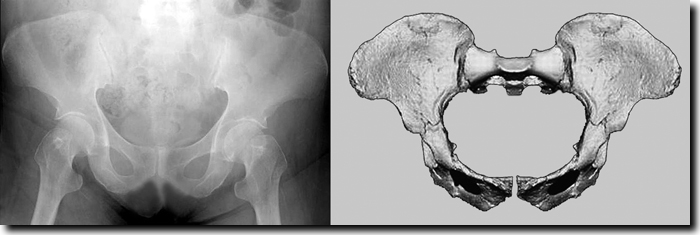

Die breiten Beckenschaufeln und die kurzen Oberschenkelknochen sind typische Merkmale für eine Entwicklungsstörung im Rahmen des Down-Syndroms (Trisomie 21).

Die breiten Beckenschaufeln und die kurzen Oberschenkelknochen von LB1 sind typische Merkmale für eine Entwicklungsstörung, wie sie im Rahmen des Down-Syndroms (Trisomie 21) auftreten. Es existieren aber zahlreiche weitere Merkmale bei LB1, die typisch für diese Entwicklungsstörung sind. Dazu gehören eine atlanto-occipitale Deformation, kleine oder fehlende Nasennebenhöhlen, eine Micrognathie (unterentwickeltes Kinn), Plattfüße, eine Brachycephalie (Rundköpfigkeit), verbreiterte Beckenschaufeln1 (Abb. 2, vgl. mit Abb. 1) und ein kleines Kleinhirn (cerebellare Hypoplasie). Insgesamt zeigt die Untersuchung der Forscher um Henneberg und Eckhardt, dass keine Merkmale von LB1 einmalig sind. Alle vom modernen Menschen abweichenden Merkmale sind krankheitsbedingt. LB1 zeigt viele Anzeichen eines missgebildeten Individuums eines modernen Homo sapiens, wie er heute im australomelanesischen Raum auf den Andaman-Inseln, Palau und auch Flores vorkommt. Die Knochenüberreste der anderen Individuen der Liang Bua-Höhle zeigen im Gegensatz zu LB1 keine eindeutig pathologischen Merkmale, wobei ihre starke Fragmentierung eine Beurteilung erschwert (Henneberg et al. 2014, siehe auch Eckhardt et al. 2014). Lediglich bei drei nicht LB1 zugehörigen Handknochenelementen sind noch nicht alle Fragen geklärt. Die Forscher um Henneberg und Eckhardt kritisieren jedoch mit Recht die methodische Qualität der bisherigen Untersuchungen der Handknochenelemente aus der Liang Bua-Höhle und die gewonnenen Schlüsse. An dieser Stelle muss betont werden, dass eine neue Menschen-Art noch nie auf der Basis von Handknochenelementen aufgestellt wurde (Eckhardt et al. 2014, Henneberg et al. 2014).

Abb. 2: Links: Röntgenbild des Beckens eines Menschen mit Down-Syndrom (mit freundlicher Genehmigung von LearningRadiology.com). Rechts: Becken von Australopithecus africanus (Stw 14) (aus Kibii et al. 2011). Das Becken des Flores-Menschen (siehe Abb. 1) ähnelt mit den seitlich ausladenden Darmbeinschaufeln („flaring ilia“) dem Becken von Menschen mit Down-Syndrom und dem Becken von Australopithecinen (siehe auch Fußnote 1).

1 Der Flores-Mensch besitzt nach Brown et al. (2004) deutlich zu den Seiten aufgeweitete Darmbeinschaufeln („ilium has marked lateral flare“). Nach Leslie Aiello ähnelt das Becken des Flores-Menschen, das deutlich weiter als das Becken des modernen Menschen ist, dem Becken eines Australopithecinen („The pelvis is virtually identical to that of an australopithecine“) (Balter 2004).